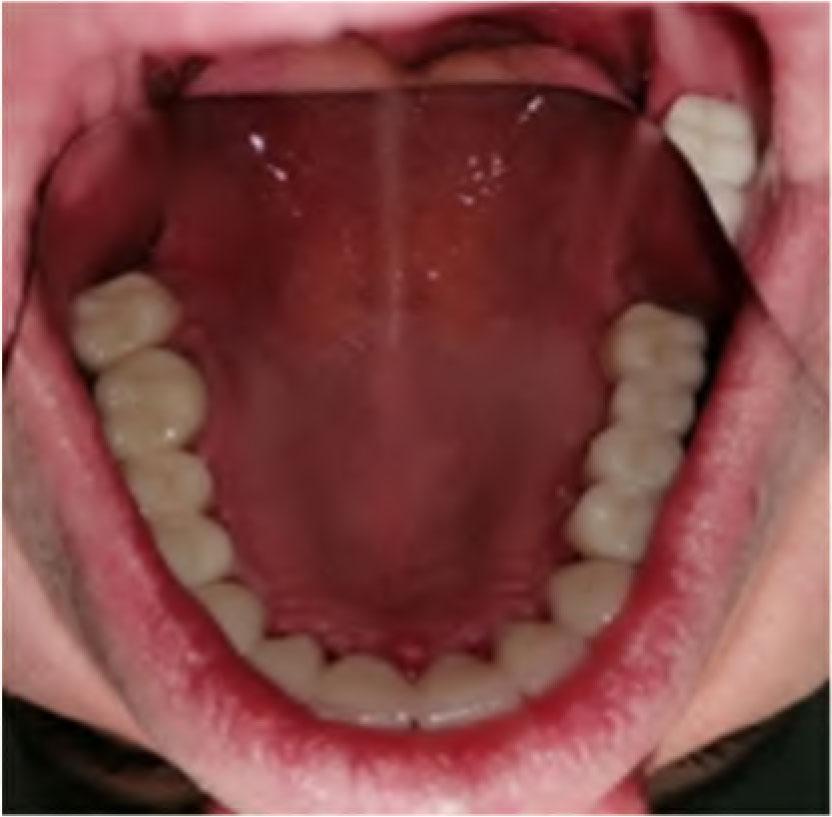

A 45-year-old male patient was referred to the Department of Prosthodontics, Faculty of Medical Sciences, University of Kragujevac with a chief complaint of protruded maxillary anterior teeth, teeth malalignment, unpleasant aesthetics and difficulty in chewing. The patient had no history of any medical problems. Extraoral examination revealed a convex profile with mild mandibular retrusion, an obtuse nasolabial angle and an everted lower lip. There was no masticatory and facial muscle hyperactivity and no signs of temporomandibular disfunction (TMD). On intraoral examination a severe deep-bite and an increased overjet with anterior maxillary protrusion were detected (Figure 1).

Initial oral examination.

The anteroposterior discrepancy of the anterior teeth was very severe and the mandibular incisal edges were occluded with the palatal tissues in the opposing arch. An overbite of 9 mm and an overjet of 12 mm were observed. There was clinical evaluation of reduced VDO. The patient’s interocclusal space that was measured between nose and chin tips was 8–9 mm (the difference between physiologic rest position of the mandible and VDO). Furthermore, facial analysis revealed that the maxillary midline was coincident with the facial midline but there was slight deviation of the mandibular midline to the right. Steiner cephalometric analysis was done. The angle of the ANB is greater than 4, by measuring it is 6. The angle of I/Spp is less than 70, by measuring it is determined to be 63. With this analysis, we determined that it is a skeletal irregularity of the II skeletal class with protrusion of the upper incisors. The patient was diagnosed as an Angle Class II division 1 malocclusion.